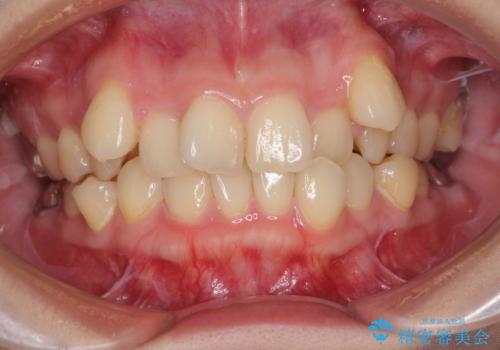

上顎の八重歯と下顎前歯の欠損 ワイヤー装置による抜歯矯正

- 上顎の八重歯を気にして来院された患者様です。

診察したところ、下顎前歯が2本欠損していたため、上下のバランスを取りながら八重歯を改善するため、上顎左右第一小臼歯2本を抜歯することとしました。

下顎前歯と本来抜歯矯正で抜歯する歯とは大きさが異なるため、仕上がりの咬み合わせは理想的なものとはなりませんでしたが、気になっていた八重歯はきれいに改善することができました。